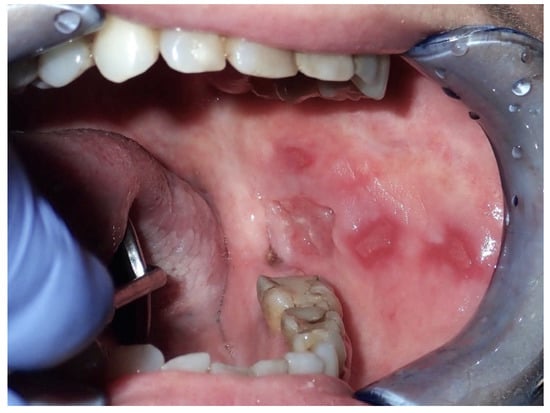

2.2. Erythroplakia

2.3. Oral Lichen Planus